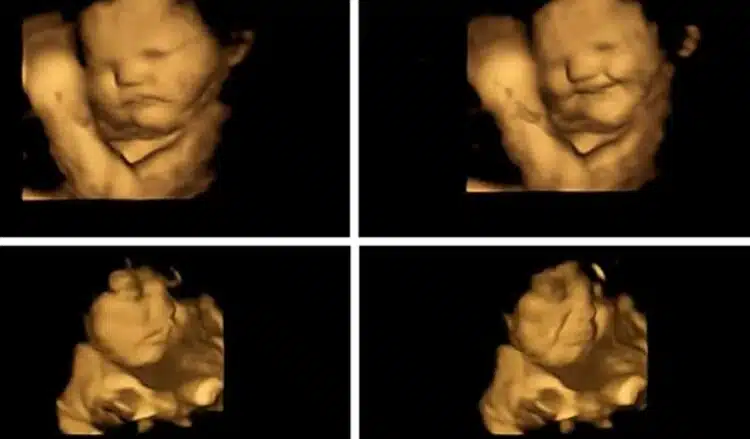

След 20 минути всички получили капсула с прах от моркови или зеле. След това е извършено сканиране и са направени снимки на мимиките на ембрионите. Според това проучване неродените бебета предпочитат моркови, които ги карат да се „усмихнат“. На зелето, между другото, ембрионите имат раздразнено изражение на лицата си.

Като част от това проучване учените стигнаха до заключението, че диетата на жените по време на бременност влияе върху хранителните предпочитания на децата в бъдеще. Ако майките спазват правилен режим на хранене по време на бременност, има вероятност бебето да развие правилни хранителни навици.